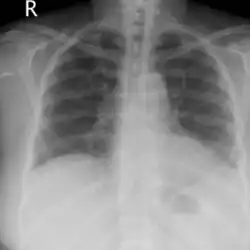

Recovery after 48 hours of supplemental oxygen

Chest x-rays of a 61-year-old female who developed salt water aspiration syndrome while swimming during a triathlon.[5]

Lung auscultation may reveal abnormal breath sounds such as rhonchi (snoring-like) or crackles (rattling), and chest imaging can show lung consolidations[4] and edema.[5] Decreased lung volumes, including a reduction of average 0.7 liters in forced expiratory volume in 1 second and vital capacity, is found on spirometry. Laboratory studies do not show specific abnormalities, but low oxygen levels in blood, slightly elevated white blood cell count and lactate dehydrogenase levels may be seen.[1]

Treatment involves supportive care with supplemental oxygen, observation and rest.[1] Most cases resolve within the first 24 hours, often spontaneously without treatment.[10] Critical care may be necessary for severe cases or cases complicated with underlying respiratory disorders.[2]